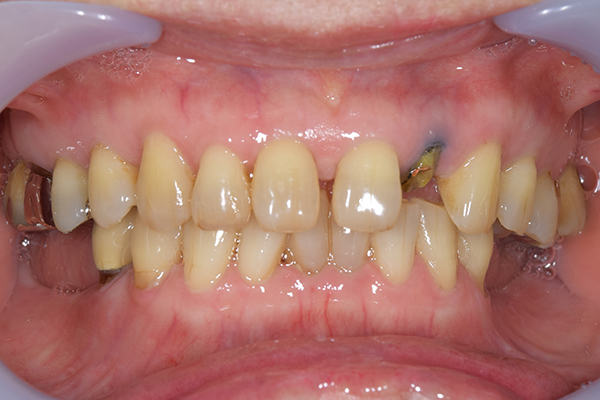

前歯が折れて当院にいらっしゃいました。 過去に下の入れ歯を作ったが、合わなくなってずっと入れ歯をいれていらっしゃらない患者様でした。 これは奥歯で噛むことができないため、前歯で噛むことを繰り返したために、負担に耐えられなくなった前歯が折れてかぶせ物ごと 外れてしまったのだと考えられます。 痛くない、違和感の少ない、下の入れ歯を作ることがこの方のゴールであると考えられました。

治療方針 長年使ってきた義歯の人工歯が磨耗し、臼歯部での咬合がすくなくなり、前歯部での接触が強くなったことで生じた前歯の破折なので、義歯も作り変える必要がある。

治療内容 前歯部MTMと同時に審美面の回復。

MTM中に義歯の作成も同時に行う。

最終的に義歯と前歯のクラウンを同時にいれる。

義歯は下顎で、しっかり噛めること、違和感の少ないものという希望があったため、なるべく入れ歯を薄く作成するために金属をしようした義歯とした。

また、見た目もあまり義歯が目立たない様に、バネの部分を見えにくいように作成した。